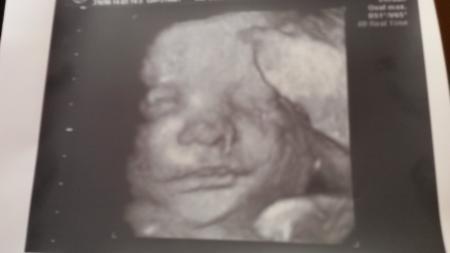

Alles gut bisher :) de kleine wiegt 1970 gramm in etwa und morgen bin ich 32+0. Anbei ein ganz putziges Foto der kleinen Maus :):)

Ups Foto vergessen :)

So süss :-) Tolles Gewicht

Schön das alles gut ist! Das Foto finde ich klasse